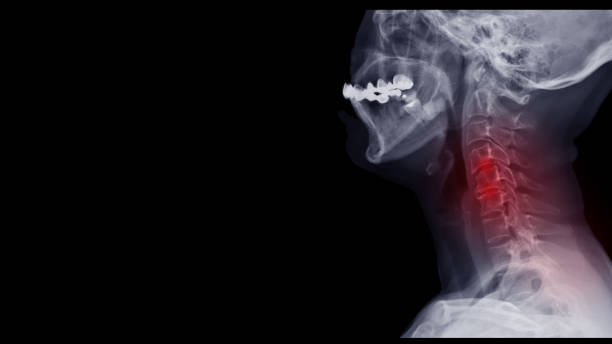

추간판 탈출증은 경추 사이의 쿠션 역할을 하는 추간판(탈장)이 밀려나와 주변 신경근을 압박하여 통증을 유발하는 질환인데 이를 목디스크라고 합니다. 높은 베개를 베고 자다가 목에 긴장을 당했을 때나 교통사고로 등으로 발생합니다. 하지만 가장 목디스크에 가장 큰 이유는 습관적인 나쁜 자세로 장기간 지속되는 나쁜 자세는 퇴행성 변화를 동반하며 40세 이후 중년층에서 목디스크는 더 흔하게 나타납니다.

목디스크가 있는 경우 가장 의심되는 증상은 어깨나 견갑골 부위에 처음 나타날 수 있는 비정상적인 감각이지만 이상하게도 저림과 통증은 없다는 것이 특징이지만 이러한 무통증이라 하더라도 디스크로 인한 감각 마비로 보는 경우가 많으며 이렇듯 목 디스크의 증상은 통증에서 무감각 및 통증에 이르기까지 다양합니다.

탈출된 디스크로 인한 통증은 탈출된 디스크가 찢어지고 척수 신경을 압박하여 상처에 염증을 일으킬 때 발생합니다. 증상은 손실된 디스크의 위치나 신경에 가해지는 압력에 따라 다른데 가장 흔하게 나타나는 증상은 인후통으로 목 뒤에서 어깨나 팔까지 통증을 유발하여 손의 감각 이상으로 이어질 수 있습니다. 이 증상에 주의를 기울이지 않으면 손가락의 감각이 둔해지고 주먹을 쥐는 힘이 약해질 정도로 심해집니다. 실수로 물 한 컵을 바닥에 떨어뜨린 적이 있다면 경추 추간판 탈출증을 의심해야 합니다. 마비된 목의 기저부에 있는 4쌍의 신경근이 경추에서 나와 어깨, 팔, 손가락에 닿기 때문에 따라서 목디스크에 좋은 운동을 미리미리 하는 것이 좋습니다.